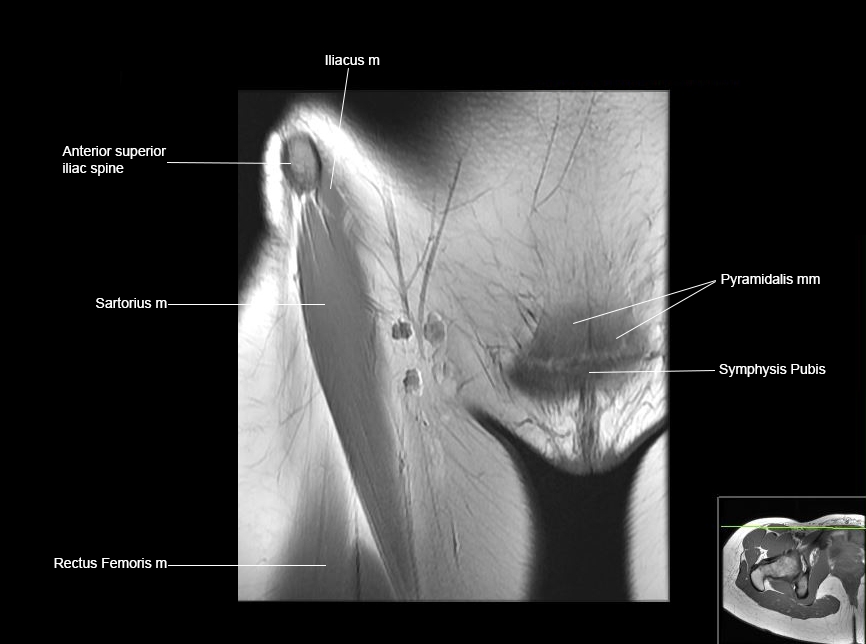

Hip

Basic Hip MRI

MRI Hip Anatomy

Scroll using the mouse wheel or the arrows